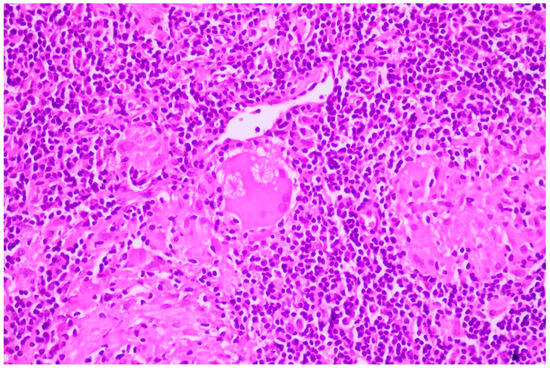

Two of the specimens with fibronodular lesions were associated with multiple NSCLC tumors of different histopathological subtypes: one case presented with adenocarcinoma (one tumor—Figure 6) and a squamous cell tumor (one tumor—Figure 7) and another case presented with adenocarcinoma (one tumor) and large-cell neuroendocrine tumors (two tumors—Figure 8).

Figure 8. Large-cell neuroendocrine cell carcinoma with abundant tumoral necrosis; HE, 40×.